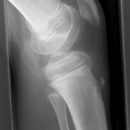

Kniegelenk